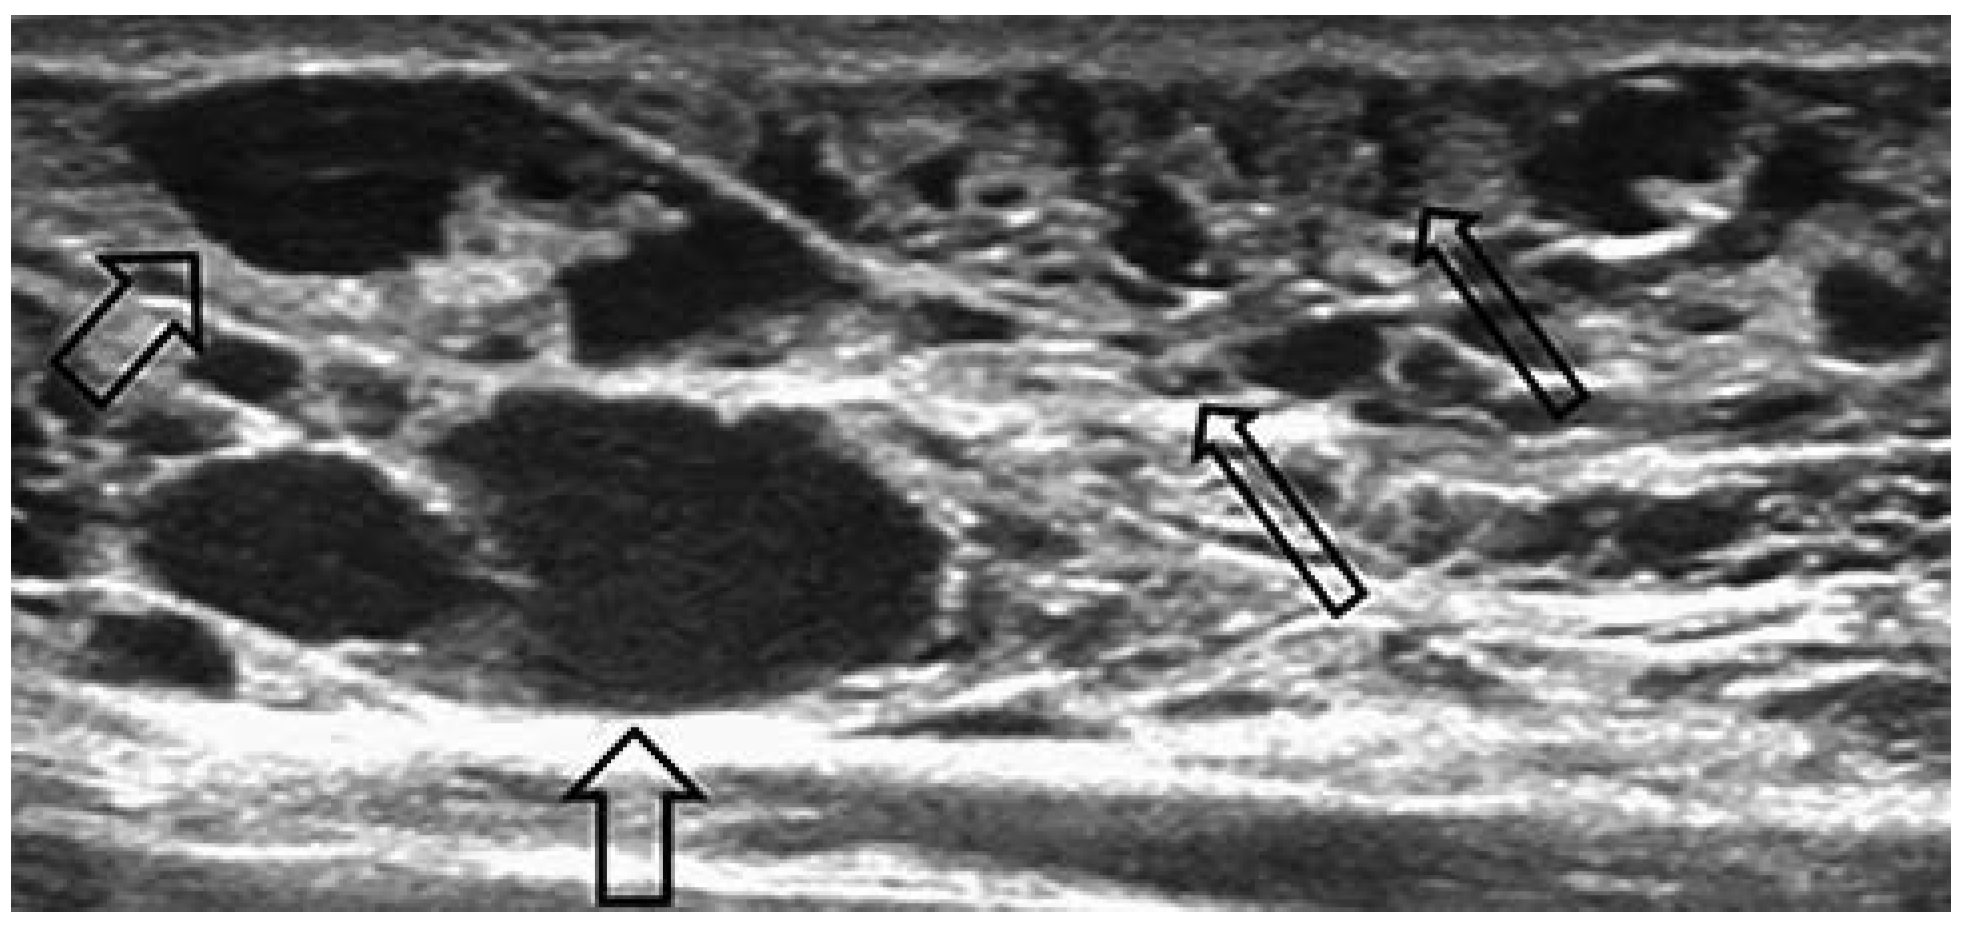

Venöse Malformationen

Lymphatische Malformation